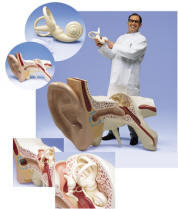

| Human Ear, Nose and

Throat - Home Page |

| After sight, hearing is the sense

that provides the brain with the most information about the outside world.

Compared with other animals, the human ear registers a fairly wide range

of sounds. These vary in volume from the delicate notes of a flute

to the ear-splitting chords of a heavy metal electrical guitar.

They vary in pitch from the deep thunderous roar of a jet engine to high

trills of a bird song. The ear has three main parts. The outer

ear consists of the ear flap and auditory canal, the middle ear contains

the eardrum and the tiny bones, the ossicles, and the inner ear comprises the

nasal shaped cochlea, semicircular canals and other fluid-filled chambers.

detect the presence of many things. The Ear, Nose and Throat are

tightly interrelated and are together treated as a medical specialty -

Otolaryngology. Our anatomical models are suitable for medical

schools and are great for patient education. |